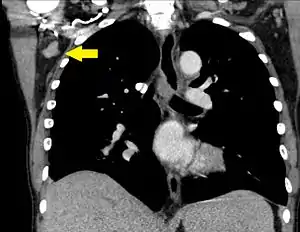

| A CT scan of axillary lymphadenopathy in a 57-year-old man with multiple myeloma. | |

Lymphadenopathy of the axillary lymph nodes can be defined as solid nodes measuring more than 15 mm without fatty hilum.[35] Axillary lymph nodes may be normal up to 30 mm if consisting largely of fat.[35]